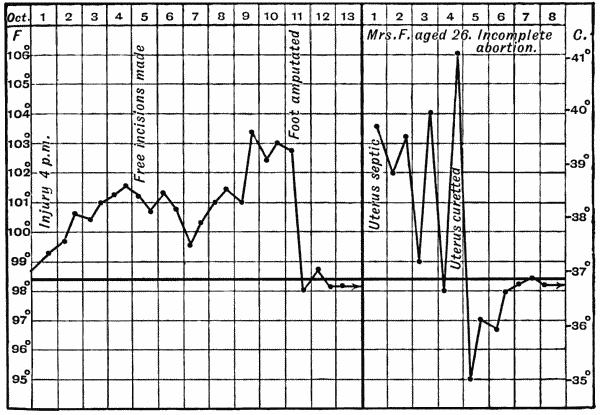

Fig. 1.—Ulcer of back of Hand covered by flap of skin raised from anterior abdominal wall. The lateral edges of the flap are divided after the graft has adhered.

| 1. | Ulcer of Back of Hand grafted from Abdominal Wall | 15 |

Another modification is to raise the flap but leave it connected at both ends like the piers of a bridge; this method is well suited to defects of skin on the dorsum of the fingers, hand and forearm, the bridge of skin is raised from the abdominal wall and the hand is passed beneath it and securely fixed in position; after an interval of 14 to 21 days, when the flap is assured of its blood supply, the piers of the bridge are divided (Fig. 1). With undermining it is usually easy to bring the edges of the gap in the abdominal wall together, even in children; the skin flap on the dorsum of the hand appears rather thick and prominent—almost like the pad of a boxing-glove—for some time, but the restoration of function in the capacity to flex the fingers is gratifying in the extreme.

Fig. 1.—Ulcer of back of Hand covered by flap of skin raised from anterior abdominal wall. The lateral edges of the flap are divided after the graft has adhered.